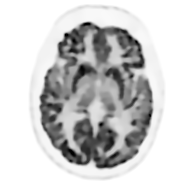

We investigated the imaging performance of a fast convergent ordered-subsets algorithm with subiteration-dependent preconditioners (SDPs) for positron emission tomography (PET) image reconstruction. In particular, we considered the use of SDP with the block sequential regularized expectation maximization (BSREM) approach with the relative difference prior (RDP) regularizer due to its prior clinical adaptation by vendors. Because the RDP regularization promotes smoothness in the reconstructed image, the directions of the gradients in smooth areas more accurately point toward the objective function's minimizer than those in variable areas. Motivated by this observation, two SDPs have been designed to increase iteration step-sizes in the smooth areas and reduce iteration step-sizes in the variable areas relative to a conventional expectation maximization preconditioner. The momentum technique used for convergence acceleration can be viewed as a special case of SDP. We have proved the global convergence of SDP-BSREM algorithms by assuming certain characteristics of the preconditioner. By means of numerical experiments using both simulated and clinical PET data, we have shown that our SDP-BSREM substantially improved the convergence rate, as compared to conventional BSREM and a vendor's implementation as Q.Clear. Specifically, in numerical experiments with a synthetic brain phantom, both proposed algorithms outperformed the conventional BSREM by a factor of two, while in experiments with clinical whole-body patient PET data (with and without time-of-flight information), the SDP-BSREM algorithm converged 35\%-50\% percent faster than the commercial Q.Clear algorithm.